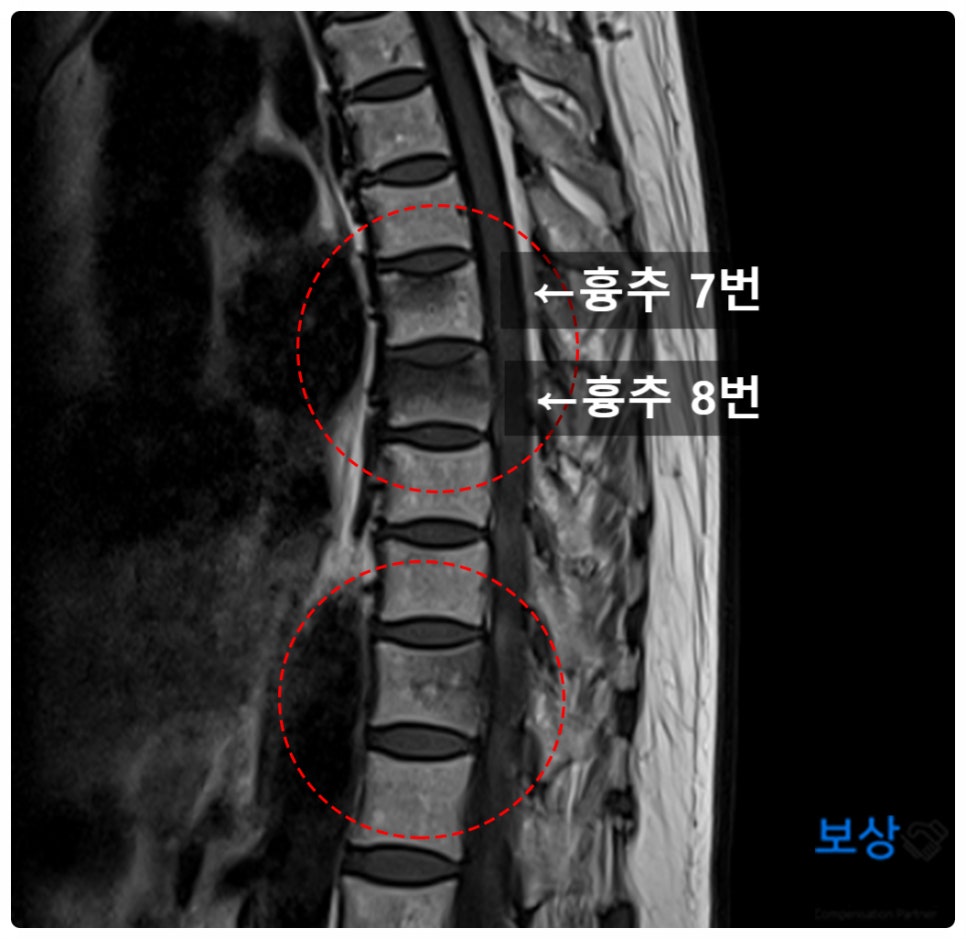

오늘 알려드릴 사례는, 60대 여성분이 헬스장에서 운동 중에 흉추 7번,8번 압박골절 당하신 사고입니다. 그럼 지금부터 부상 후에 어떻게 상해후유장해 보험금 청구하였는지, 그 과정을 자세히 설명드리겠습니다.

결국 내원하여 등뼈 부분을 엑스레이 및 MRI 촬영으로 정밀 검사를 시행하였습니다.

검사 결과는 뜻밖에도 척추압박골절이었는데요. 특히 등쪽의 흉추 7,8번이 심하게 찌그러졌습니다. 이 경우에 피해자가 비교적 고령이었기 때문에, 골밀도 검사(BMD)도 함께 진행하게 되었습니다.

골밀도 수치는 T-socre : -2.2로서 골다공증은 아니었지만, 골감소증에 해당하였습니다. (-2.5 이하면 골다공증 판정) 그리고 다행히도 척수 신경 침범이 없는 안정형 골절이었기에, 척추 보조기 착용하며 약 12주간 안정가료를 필요로 하였습니다.